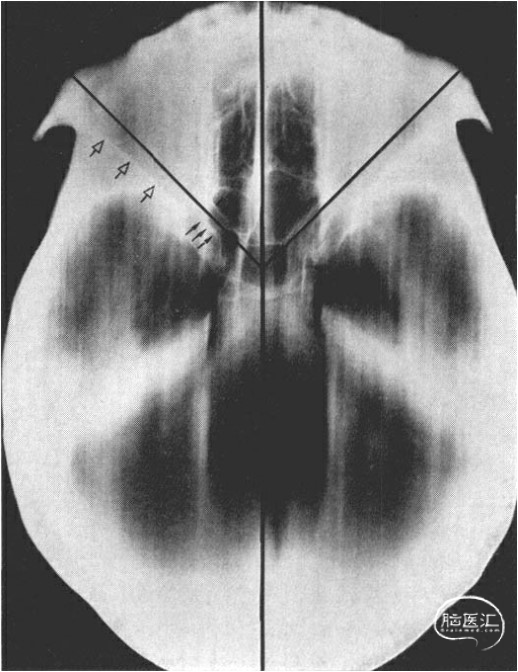

颅底的颅内视图,显示患者头部转动的角度,以允许手术显微镜垂直接近。

颅底相应的X射线照片,以说明平行于眶侧壁的视神经的角度。